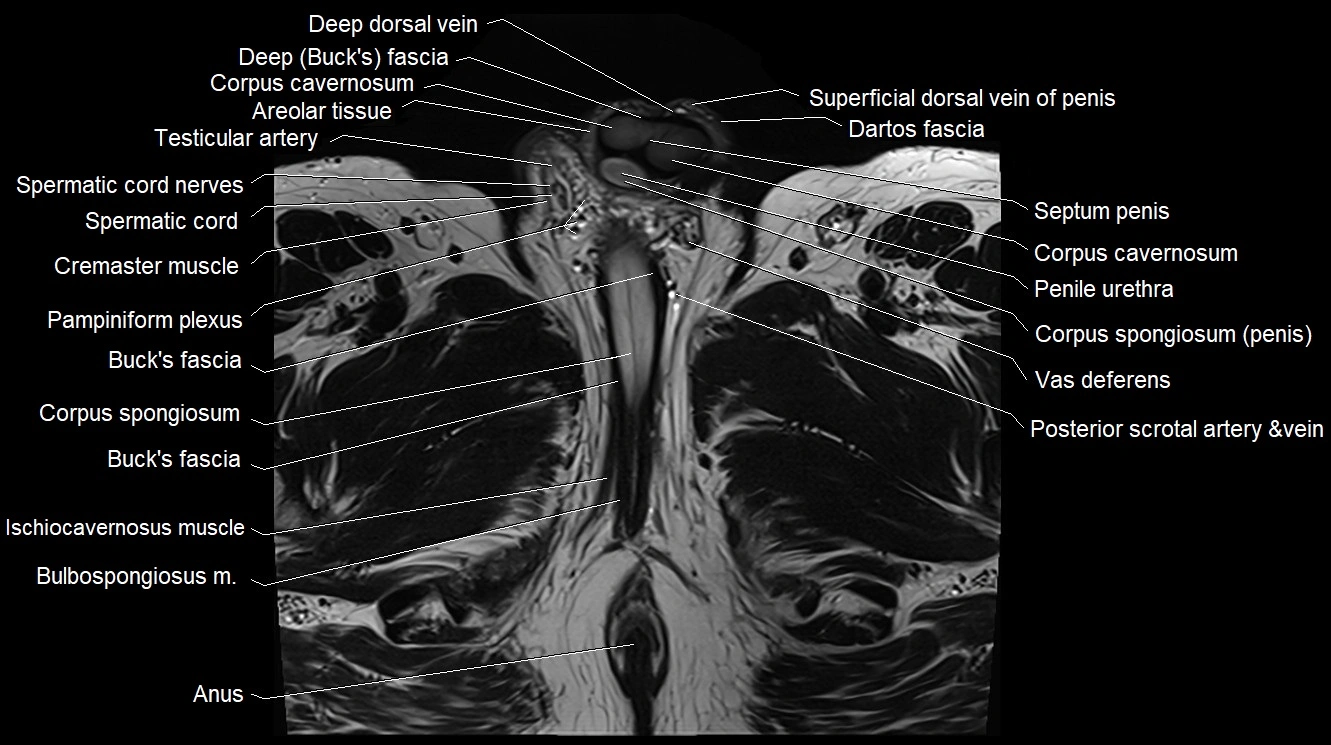

- Buck's fascia (Deep fascia of penis)

- Corpus cavernosum

- Corpus spongiosum

- Cremaster muscle

- Dartos fascia

- Deep dorsal vein of penis

- Pampiniform plexus

- Penile urethra

- Septum of the penis (Penile septum)

- Spermatic cord

- Spermatic cord nerves

- Superficial dorsal vein of penis

- Testicular artery

- Vas deferens